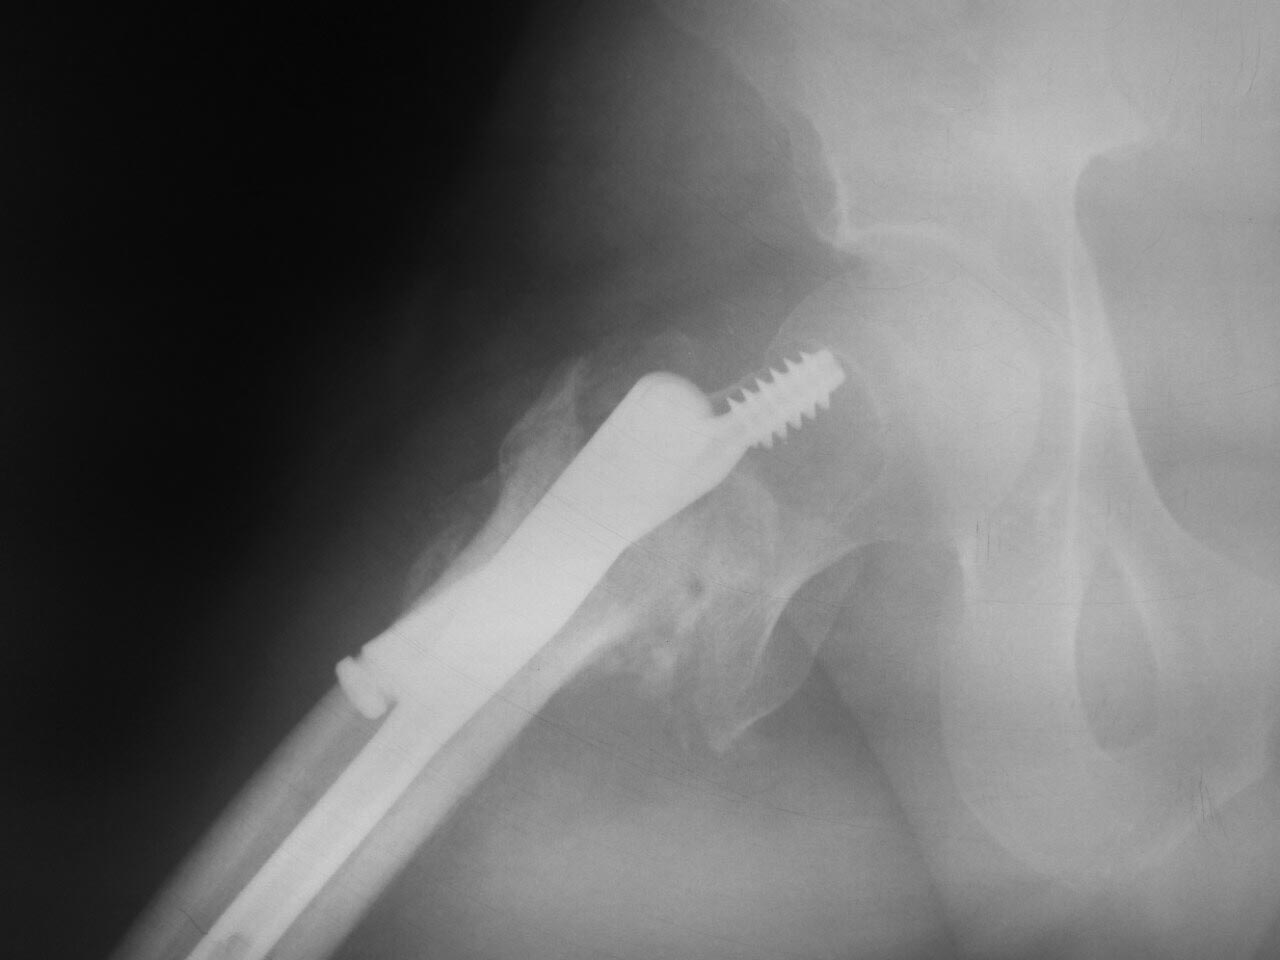

Выполнен остеосинтез Gamma3 1,5 мес назад |

Уважаемые коллеги, посоветуйте, пожалста, как исправить ситуацию. Мужчина 45 лет 1,5 мес назад прооперирован в одной из клиник в средней полосе. Выполнен остеосинтез, видимо , Gamma 3.

Сказали - ходи. В общем, сейчас ходит на костылях дозированно нагружая ногу. Вернувшись из отпуска пришёл к нам в клинику, озадачил коллег)) . Есть следующие мысли: 1. Удалить гамму , остеосинтез DCS с длинной накладкой и костной пластикой. 2.Реостеосинтез имеющимся у нас гамма-гвоздём с деротационным винтом, установив его в правильное положение. Коллеги, помогите в принятии решения, дополните пробелы в наших изысканиях. Заранее огромное спасибо за помощь!